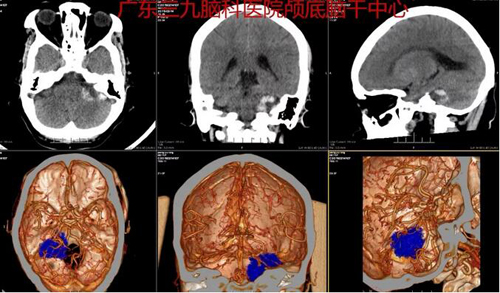

图1:术前CTA示左侧听神经增粗、强化。邻近左侧桥臂受压